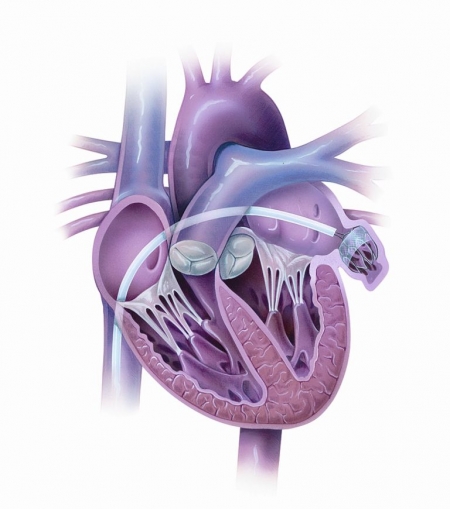

Ученые подтвердили эффективность устройства-сторожа, которое препятствует образованию тромбов, приводящих к инсульту